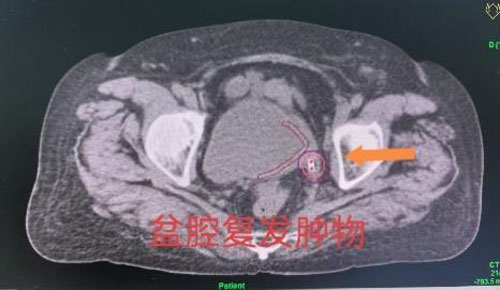

刘红教授和妇产超声科王翠菊教授团队为来访专家展示了两例疑难病例插植放疗操作的全过程。一名患者为宫颈癌IIIC1R期盆腔闭孔区域淋巴结转移。淋巴结转移是宫颈癌最常见的转移路径,同时也是影响宫颈癌患者预后最主要的危险因素之一,转移淋巴结通常需要更高的放疗剂量才能获得更好的局部控制效果。通过该项技术,在后装治疗过程中可以同时实现宫颈肿物和转移淋巴结的同步推量照射,在保护危及器官的同时,给予转移淋巴结更高的放射剂量,从而获得更好的肿瘤局部控制效果。另一名患者为宫颈癌术后膀胱后壁肿物复发。肿物体积越小,治疗效果越好,放疗的副损伤越小,但是,体积越小的肿物越难做到精准插植治疗。经腔内超声实时引导的插植技术,可以实现对微小肿物的精准定位,在确保不损伤膀胱的前提下,精准实现盆腔复发肿物的近距离放疗。

近距离放疗技术凭借其显著优势切实造福了许多患者。一名宫颈癌术后盆腔侧壁复发的患者,经过外照射联合经腔内超声引导的近距离放射治疗,放疗结束1个月后盆腔肿物完全消失;一名子宫内膜癌术后膀胱后壁复发的患者,没有外照射,只接受6次精准的腔内超声引导的近距离照射就完成了60Gy的根治性放疗剂量,放疗结束3个月后,肿物完全消失……妇瘤科将持续提升医疗技术,以精准化诊疗为基石、个性化方案为特色、人性化服务为内核,以高质量医疗服务为患者健康保驾护航。